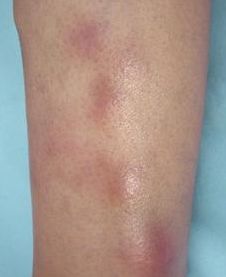

1. 皮肤表现:出现紫红色或淡紫色的扁平丘疹,表面光滑且有光泽,边界清晰。皮疹常呈多角形,可融合成片状,多见于手腕、前臂、踝部和小腿。患者常伴有剧烈瘙痒。